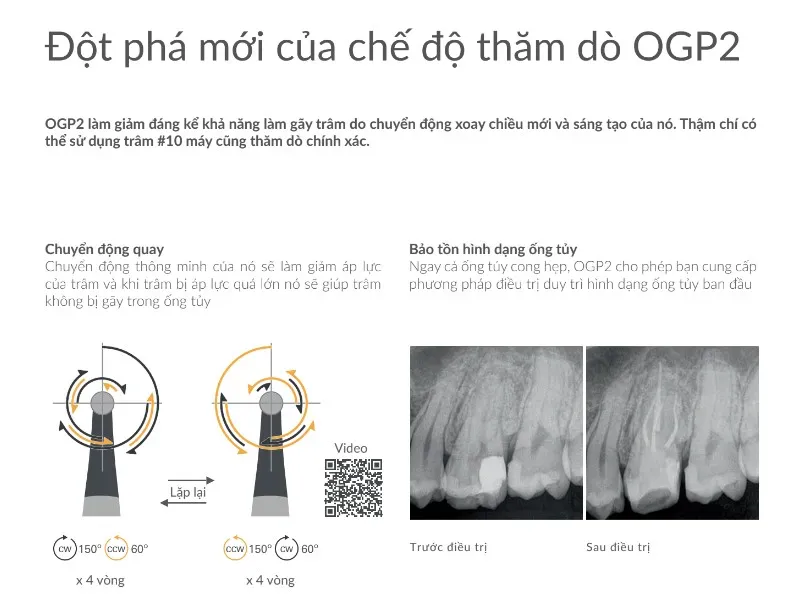

Giải phẫu tủy răng và sửa soạn lối vào nội nha

Giới thiệu Thực hành nội nha thành công được xây dựng trên nền tảng kiến thức sâu sắc...

Giới thiệu Thực hành nội nha thành công được xây dựng trên nền tảng kiến thức sâu sắc...